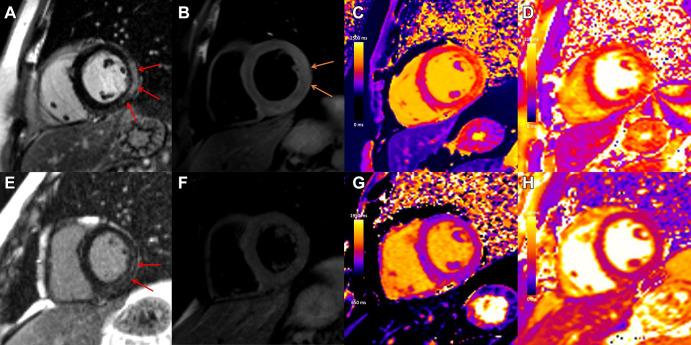

Myocarditis is a nonischemic inflammatory disease of the myocardium that can be triggered by a multitude of events, including viral infection and toxins. Recently, there has been heightened interest in myocarditis given its association with COVID-19 vaccination. Timely identification of myocarditis can affect patient management and prognosis. Therefore, it is crucial for radiologists and cardiac imagers to understand the role of cardiac imaging to establish a diagnosis and inform treatment decisions. Cardiac MRI is the most important noninvasive imaging modality for evaluation of myocarditis, with typical findings of focal or diffuse myocardial edema and myocardial damage, including presence of late gadolinium enhancement. There are currently limited data available to indicate that the pattern of myocardial injury following COVID-19 vaccination is similar to other causes of myocarditis, although the severity of disease may be relatively mild. A description of the role of imaging and typical imaging features will be reviewed here, with a focus on emerging data in the setting of myocarditis after COVID-19 vaccination. MRI, Heart, Inflammation © RSNA, 2021.

心肌炎是一种心肌的非缺血性炎症性疾病,可由多种因素引发,包括病毒感染和毒素。近来,鉴于心肌炎与新冠病毒疫苗接种之间的关联,人们对其兴趣大增。及时识别心肌炎会影响患者的管理和预后。因此,放射科医生和心脏影像专家了解心脏成像在确立诊断及指导治疗决策方面的作用至关重要。心脏磁共振成像(MRI)是评估心肌炎最重要的非侵入性成像方式,其典型表现为局灶性或弥漫性心肌水肿以及心肌损伤,包括钆剂延迟强化的存在。目前仅有有限的数据表明,新冠病毒疫苗接种后心肌损伤的模式与心肌炎的其他病因相似,不过疾病的严重程度可能相对较轻。本文将回顾成像的作用及典型成像特征,重点关注新冠病毒疫苗接种后心肌炎相关的新出现数据。MRI、心脏、炎症 © RSNA,2021年